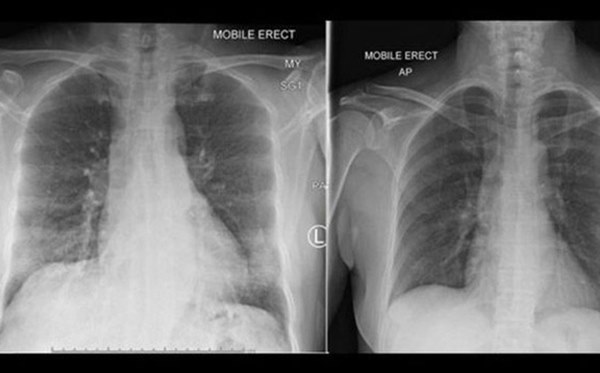

Phổi của bệnh nhân COVID-19 đã giảm mờ đục sau khi tế bào miễn dịch xuất hiện. Ảnh: BBC

Tổ chức Y tế Thế giới (WHO) cho biết triệu chứng của COVID-19 chủ yếu là sốt, ho và khó thở, khi chụp ảnh phổi có dấu hiệu xơ. Dịch bệnh bùng phát vào cuối tháng 12/2019, làm hàng chục người lây nhiễm, sau đó tiếp tục lây lan sang 162 quốc gia và vùng lãnh thổ trên thế giới.